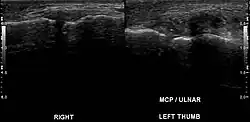

| Stener lesion on left thumb in ultrasound | |